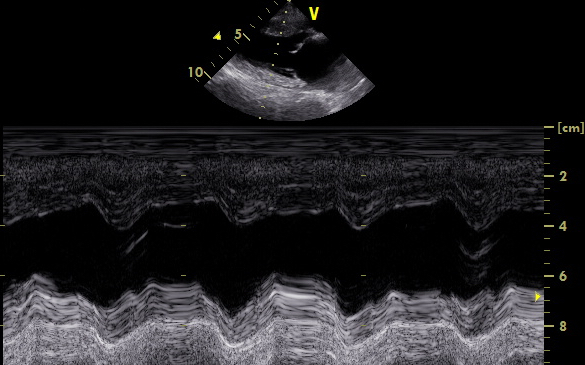

Es gibt verschiedene Ursachen für diese Form der Arrhythmie, welche mit Hilfe einer Echokardiographie weiter abgeklärt werden können. Daher wurde dem Besitzer als nächster diagnostischer Schritt ein Herzultraschall angeraten. Hierfür liegt der Hund auf einem speziellen Tisch und wird in rechter und linker Seitenlage geschallt. Im Herzultraschall zeigte sich in den Phasen, in denen „Astor“ die Rhythmusstörung hatte, eine stark verminderte Pumpleistung des linken Ventrikels mit einem subjektiv vergrößerten linken Herz (Hauptkammer und Vorkammer). Was sich dann auch in den Messwerten bestätigte. In Phasen, in denen der Herzschlag einen normalen Rhythmus hatte, war die Pumpleistung etwas besser, die Messwerte lagen im Graubereich. Der linke Vorhof war leicht vergrößert. Neoplasien oder Veränderungen im Herzmuskel konnten nicht dargestellt werden.

Ende Mai wurde dann „Astor“ erneut zur Ultraschallkontrolle vorgestellt. Ihm ging es nach wie vor gut. Im Ultraschall zeigte sich eine deutlich verbesserte Pumpfunktion des linken Ventrikels. Alle Messwerte lagen wieder im Referenzbereich. Eine weitere Untersuchung im August zeigte stabile Werte.